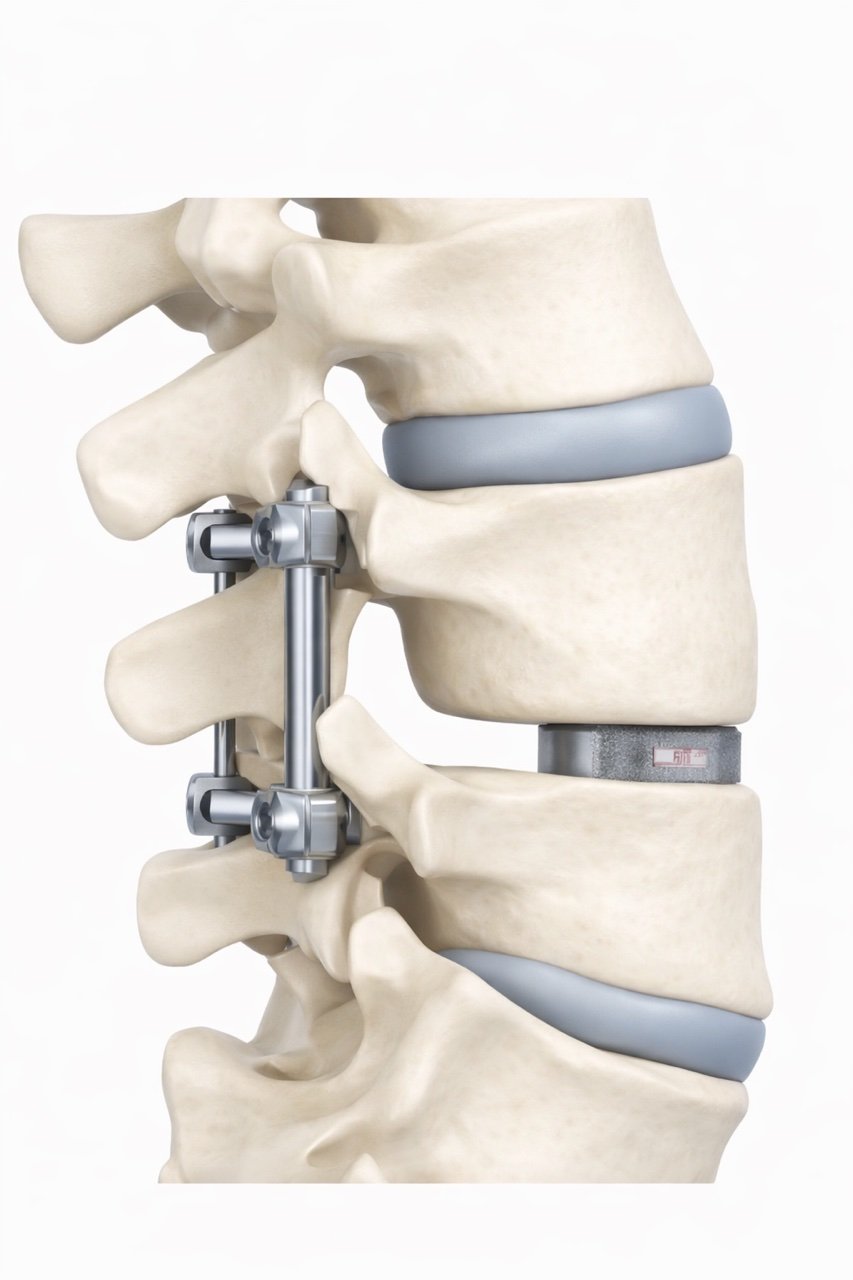

A medical model of a human spine showing vertebrae, intervertebral discs, and surgical hardware.

A Transforaminal Lumbar Interbody Fusion (TLIF) is a type of spinal fusion surgery performed through an incision in the back of the spine.

1. Pressure on the spinal nerves is relieved.

2. The damaged disc between two vertebrae is removed.

3. A spacer (interbody cage) filled with bone graft is placed into the disc space.

4. Screws and rods are used to stabilize the spine.

Over time, the bone graft allows the two vertebrae to grow together into a solid bone, which stabilizes the spine.